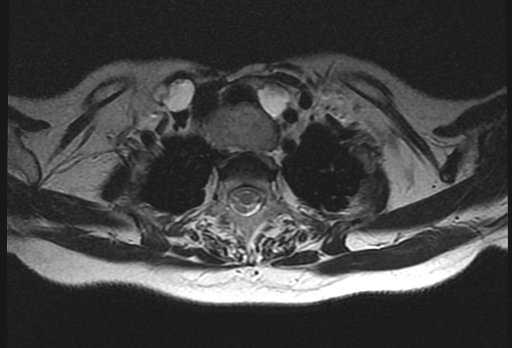

- Томографию. С помощью магнитно-резонансной томографии возможна дифференциация рака щитовидной железы от доброкачественного узлового образования. Компьютерная томография щитовидной железы дает возможность уточнить стадию заболевания. Основным методом верификации рака является тонкоигольная биопсия щитовидной железы с последующим гистологическим исследованием биоптата.

КТ шеи. Инвазивная опухоль щитовидной железы (красная стрелка) с прорастанием в трахею (синяя стрелка).

Магнитно-резонансная томография (МРТ) позволяет получить детальную топографо-анатомическую картину опухоли и ее соотношение с органами и структурами шеи. Это необходимо при планировании хирургического лечения в случае инвазии опухоли в соседние структуры.